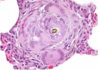

features of fibroblasts/myofibroblasts

- webbed cytoplasm

- stretched nucleus

role of fibroblast/myofibroblast

- ‘Prolonged inflammation with associated repair’

- Role in generation and repair

- Produce and secrete and lay down collagen- helping to reconstruct tissue